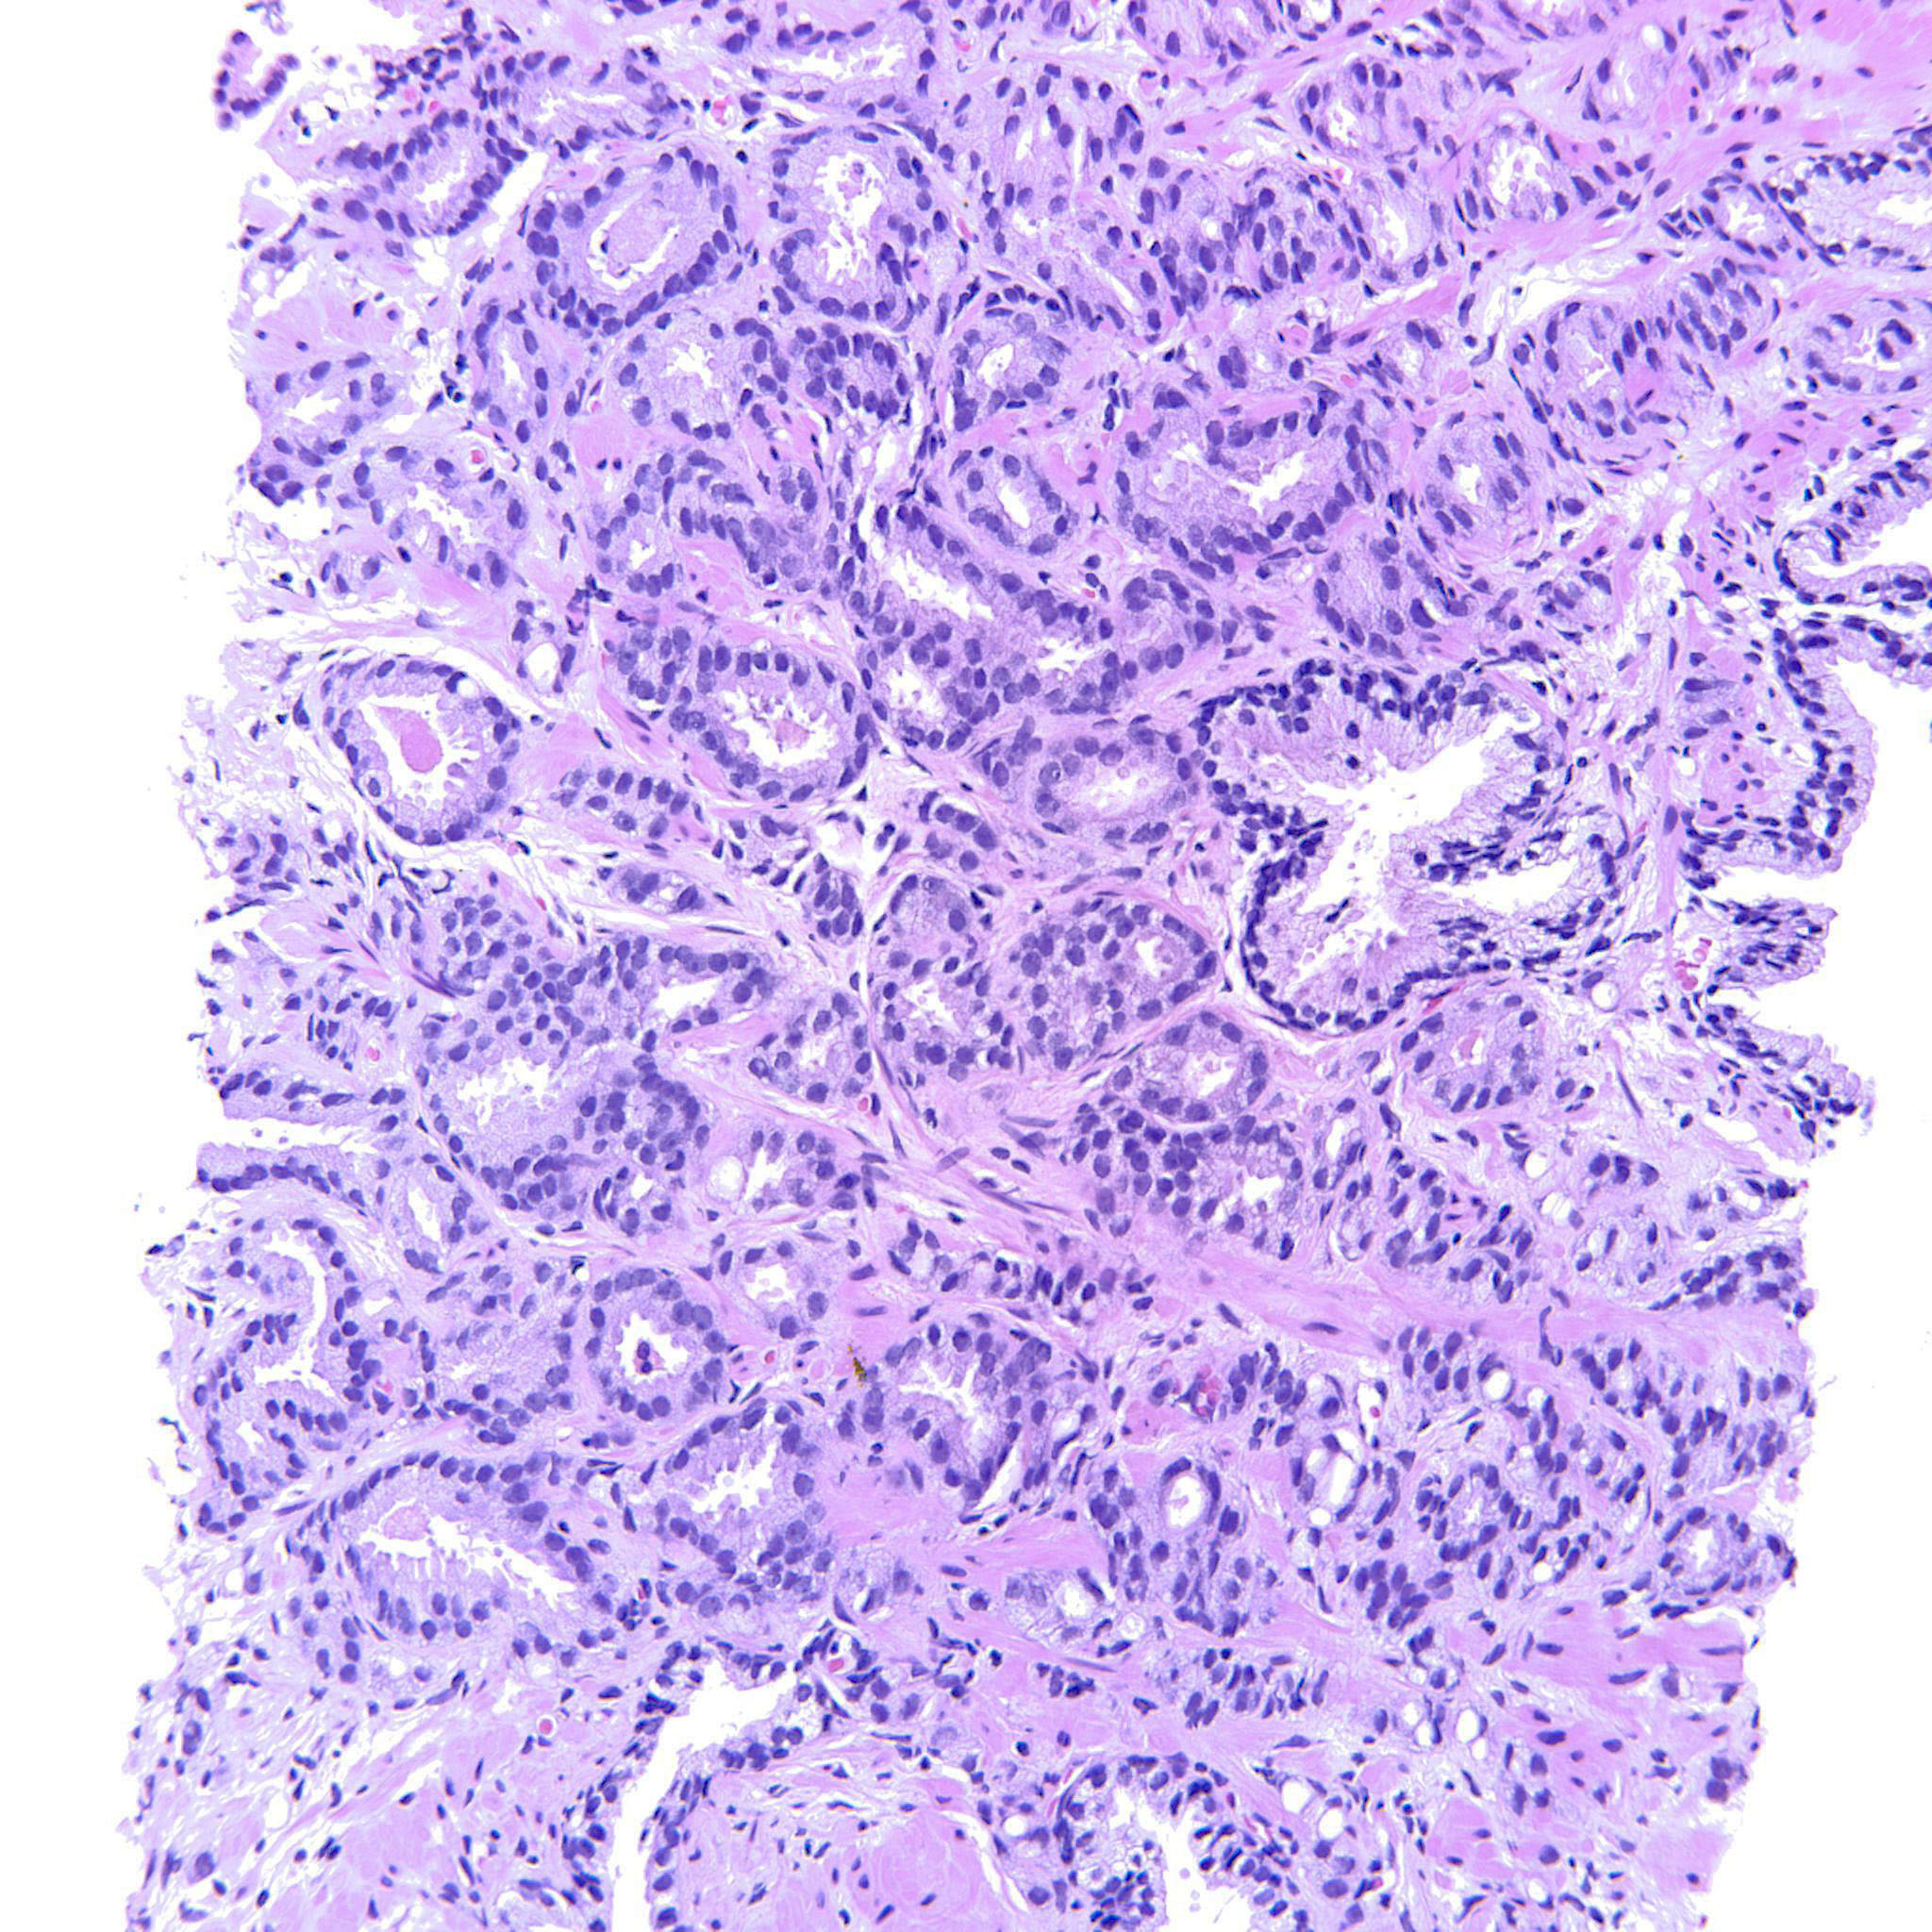

Prostate cancer grading

Case ID: 760